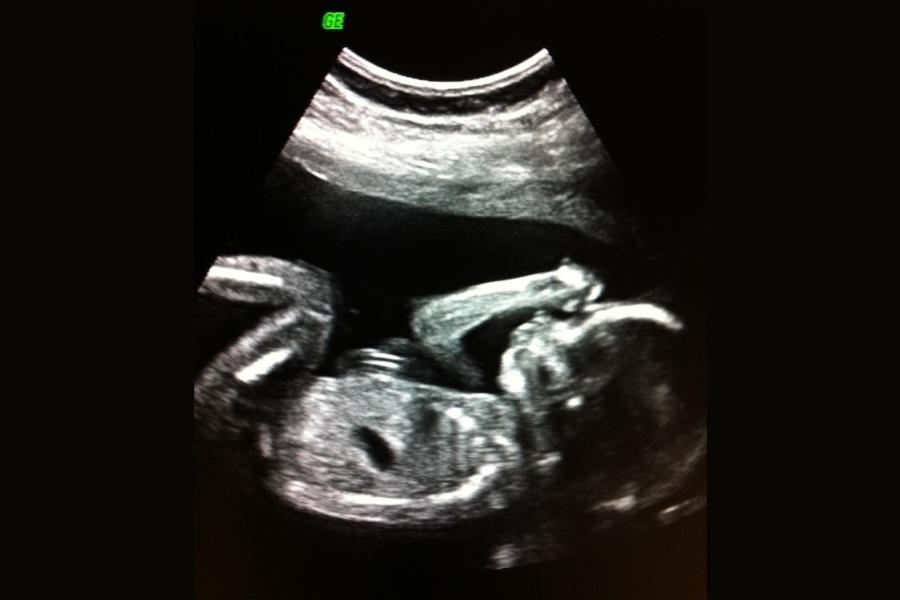

Tilvækstscanning for at se, hvordan barnet vokser Til udvidet fosterdiagnostik hører også vækstkontrol med ultralyd, ofte kaldet tilvækstscanning. Ved undersøgelsen estimeres barnets vægt og sammenlignes med den forventede vægt for graviditetslængden. En tilvækstscanning udføres rutinemæssigt, hvis du f.eks. tidligere har født et væksthæmmet barn, har en diagnose eller risikofaktor, der kan påvirke barnets vækst, eller hvis din SF-måling er afvigende.

Hvis undersøgelsen udføres på et enkelt tidspunkt kaldes det vægtestimation. Hvis den udføres flere gange, kan man følge barnets vækst over tid. I nogle tilfælde kontrolleres også blodgennemstrømningen i navlestrengen og mængden af fostervand for at få et helhedsbillede af, hvordan barnet har det.